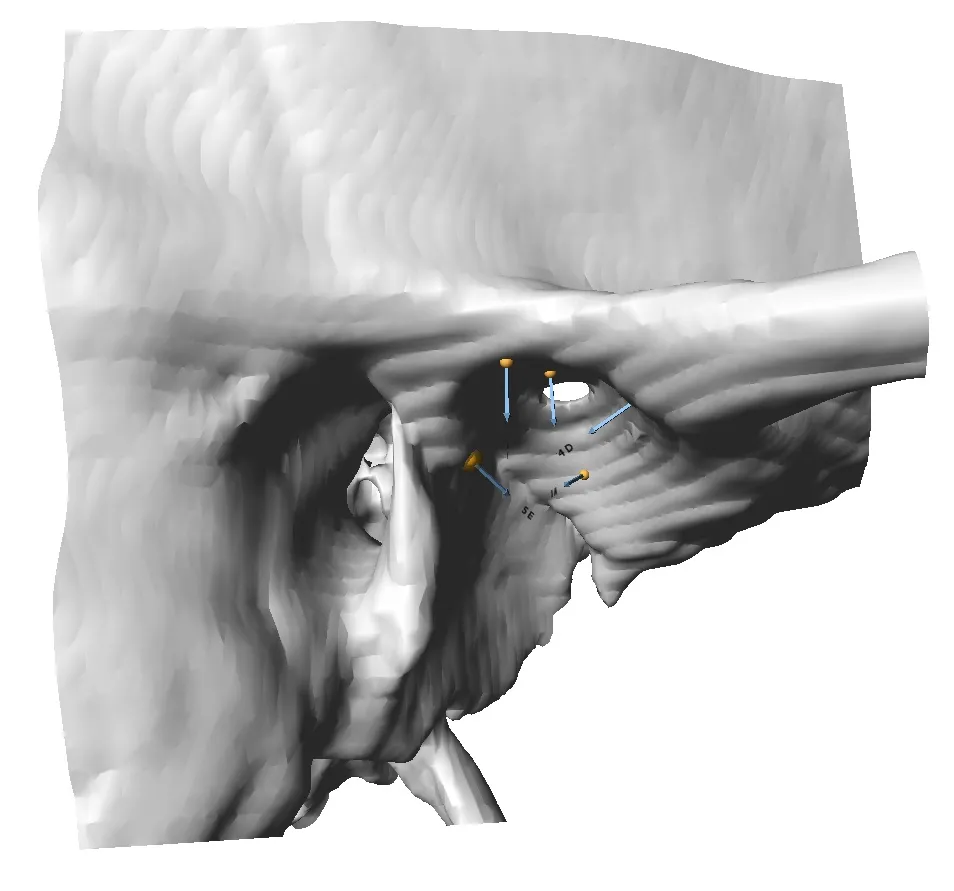

Collect Landmark Points

Place landmark points, curves, and patches, with automatic generation of semi-landmark points along curves and patches. Export landmarks to common file formats.